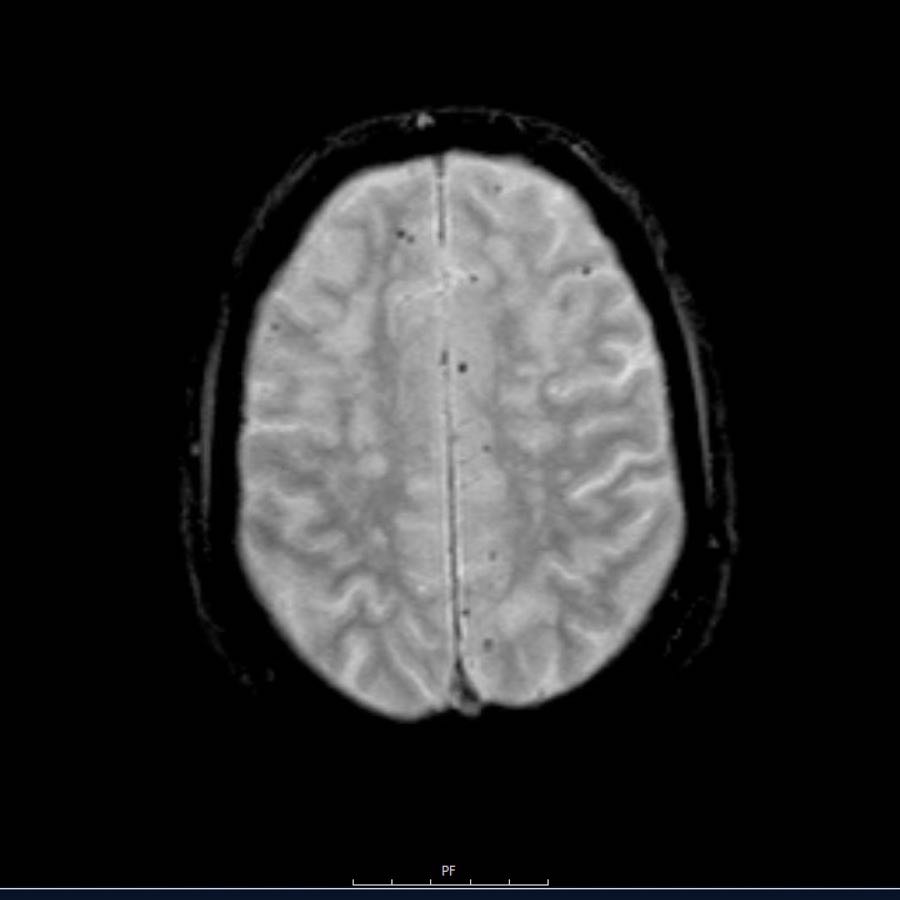

Các ổ xuất huyết nhỏ này còn được gọi là xuất huyết vi thể (microbleeds).

Lưu ý số lượng rất nhiều các ổ xuất huyết nhỏ này, phân bố chủ yếu ở vùng ngoại vi của não.